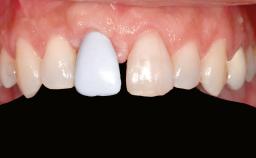

Ridge Preservation and Implant Placement for a Fixed Dental Prosthesis After a Car Accident

Prosthesis Type FDP

Defining Characteristics Up to three missing teeth to be replaced with an implant-borne restoration or restorations